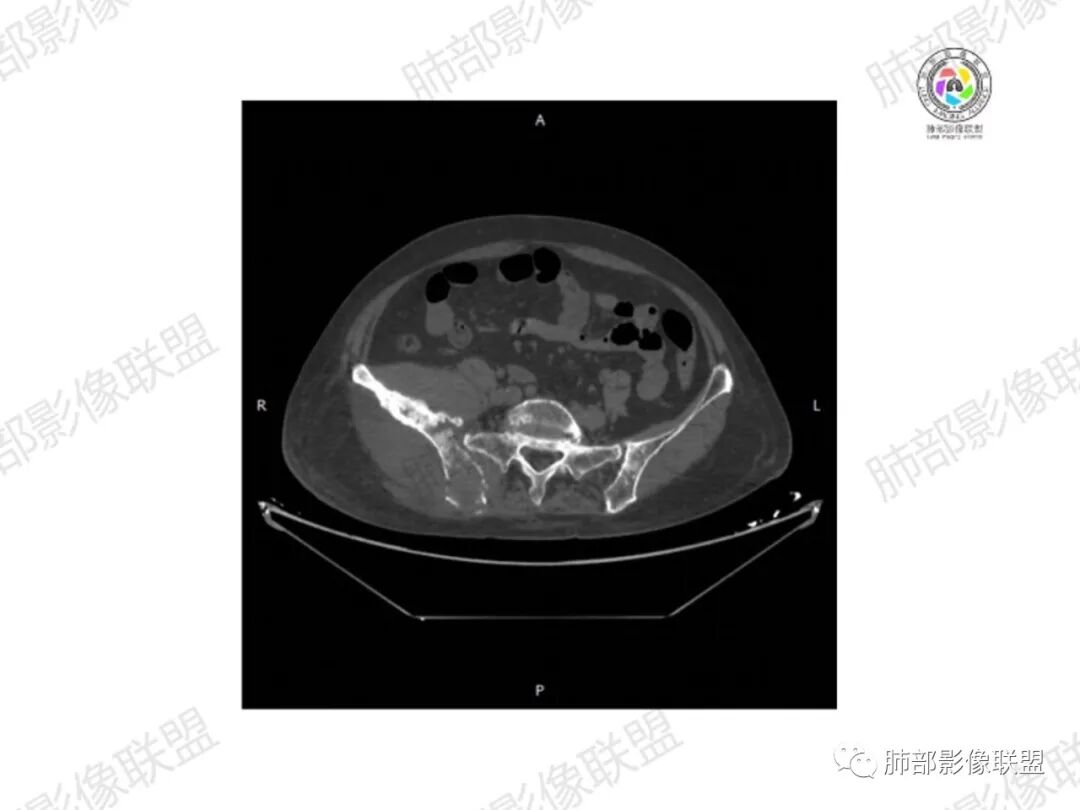

2.右髂骨轻度变形伴广泛骨质吸收破坏,边界不清且突破骨皮质。近中线区以溶骨性破坏为主,髂骨翼一侧则成骨性改变明显,骨表面见垂直骨针或花边样高密度瘤骨。

3.患骨多处皮质断裂,符合病理性骨折。注意折端可能会形成骨痂,但本例无论是形态还是部位都不符合骨痂。

4.患骨两旁(即盆骨内外)见边界不清的较大范围软组织快影,其间偶见骨化影。

1.边界不清的骨质吸收破坏,溶骨明显,骨皮质突破,软组织肿块,种种迹象表明其恶性无疑!

2.但注意这是有“成骨”的恶性骨肿瘤!我们知道老年患者的骨原发性恶性肿瘤“成骨”非常少见。少数转移瘤可为成骨型或混合型,女性患者如乳腺癌骨转移等。在男性,最典型的成骨转移是前列腺癌。

本例右侧髂骨具有较为典型的“骨肉瘤”影像学特征,有边界不清的吸收破坏、有新生骨、形成软组织肿块等等。

4.“成骨肉瘤”绝大多数发生于青少年,发生于老年患者则往往见于其他因素,如诱发于畸形性骨炎(Paget病,本例影像不支持),骨照射、骨坏死等。其他如骨旁骨肉瘤等,发病年龄可以偏大。